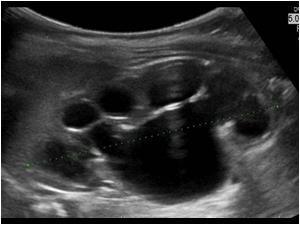

Bebeklerde hayatın ilk aylarında ciddi kusmalar ve kilo alımlarında eksiklik olması durumunda mide çıkışında darlık düşünülür. Pilor stenozu adını verdiğimiz bu durumda mide çıkışında darlık olduğu için mideden on iki parmak bağırsağına besinlerin geçişi yavaşlar, mide aşırı dolduğu içinde beslenmeden hemen sonra bebek kusar. Pilor stenozu ultrason ile rahatlıkla saptanabilir. Bu durumda bebekte gelişim problemlerine yol açmamak için cerrahi olarak darlık bölgesi gevşetilir.